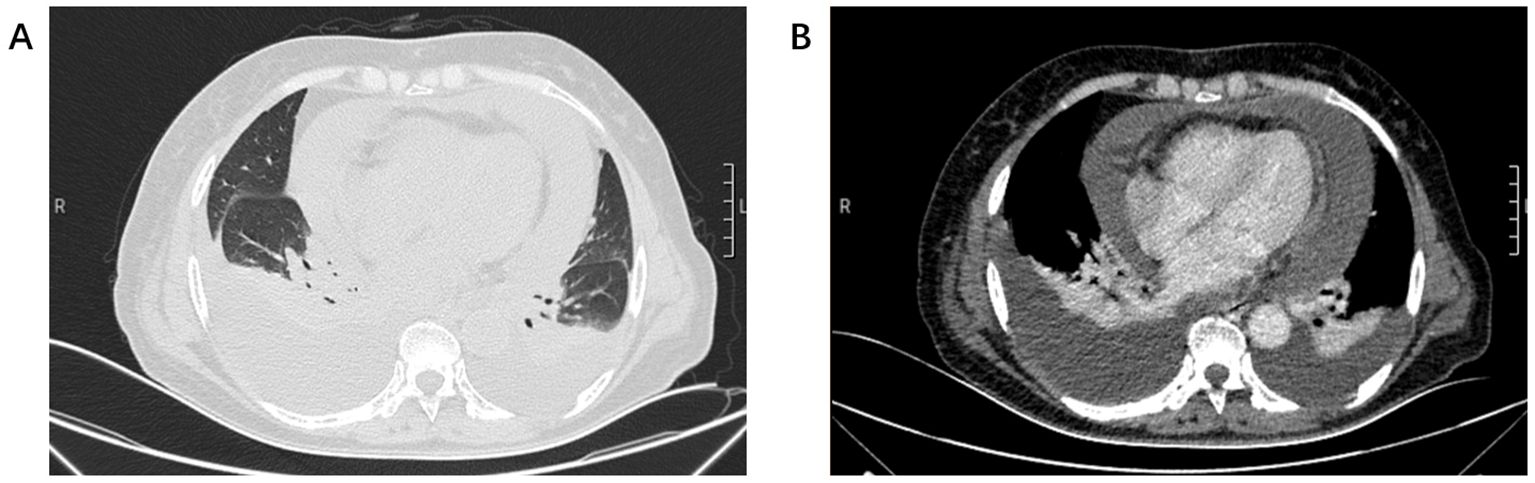

BRAF V600E mutation defines a rare but targetable subset of NSCLC. We report a 70-year-old non-smoking woman with unknown primary lung adenocarcinoma presenting with multistation mediastinal lymph-node metastases and massive malignant pleural and pericardial effusions. Molecular profiling showed BRAF V600E mutation and high PD-L1 expression(TPS 90%, CPS 95). The patient received combined dabrafenib, trametinib, and pembrolizumab with close safety monitoring, achieving rapid tumor control and complete remission by six months with manageable toxicity. This case suggests that early integration of PD-1 blockade with BRAF/MEK inhibition treatment may benefit selected patients and underscores the value of comprehensive molecular and immunohistochemical assessment to guide individualized therapy.